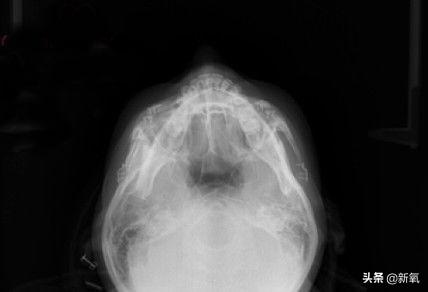

从头顶上来看,经过上次颧骨内推之后,她的颧骨两侧高低不一样,有些不对称,所以这次进行了修复矫正。